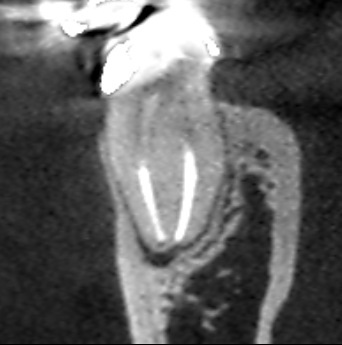

初診時の下顎第一大臼歯の近心根の冠状断のCT画像です。

根の先に膿の影がみられます。赤い矢印の先に2本の根管充填がみられます。この根管と根管の間にイスムスがあり、そこに残存している神経組織が腐敗し根管を汚染していることも考えられます。